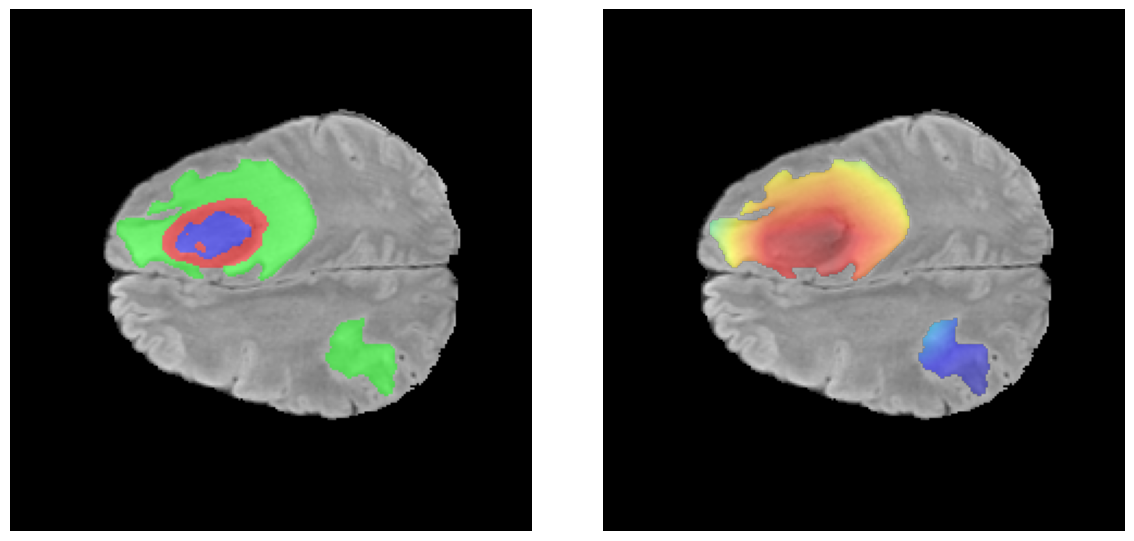

Mapas de Explicabilidad (Grad-CAM++)

Visualización de las regiones de atención del modelo que validan su razonamiento clínicamente relevante

Ejemplos HGG - Atención en Núcleo Necrótico y Tumor Realzado

Los heatmaps muestran que el modelo concentra su atención en las regiones de Tumor Realzado (rojo) y Núcleo Necrótico (azul), características patológicas clave de los gliomas de alto grado.

Ejemplos LGG - Atención Difusa en Edema Peritumoral

Para casos LGG, la atención del modelo es más difusa y se concentra principalmente en la región de Edema Peritumoral (verde), consistente con la naturaleza más infiltrativa y menos agresiva de estos tumores.

El análisis Grad-CAM++ reveló que el modelo desarrolla automáticamente la capacidad de localizar las regiones tumorales. Para casos HGG, la atención se alinea fuertemente con las regiones de Tumor Realzado (ET) y Núcleo Necrótico (NCR). En contraste, los casos LGG muestran atención más difusa, principalmente concentrada en la región de Edema Peritumoral (ED), lo cual es consistente con la patofisiología conocida de los gliomas.